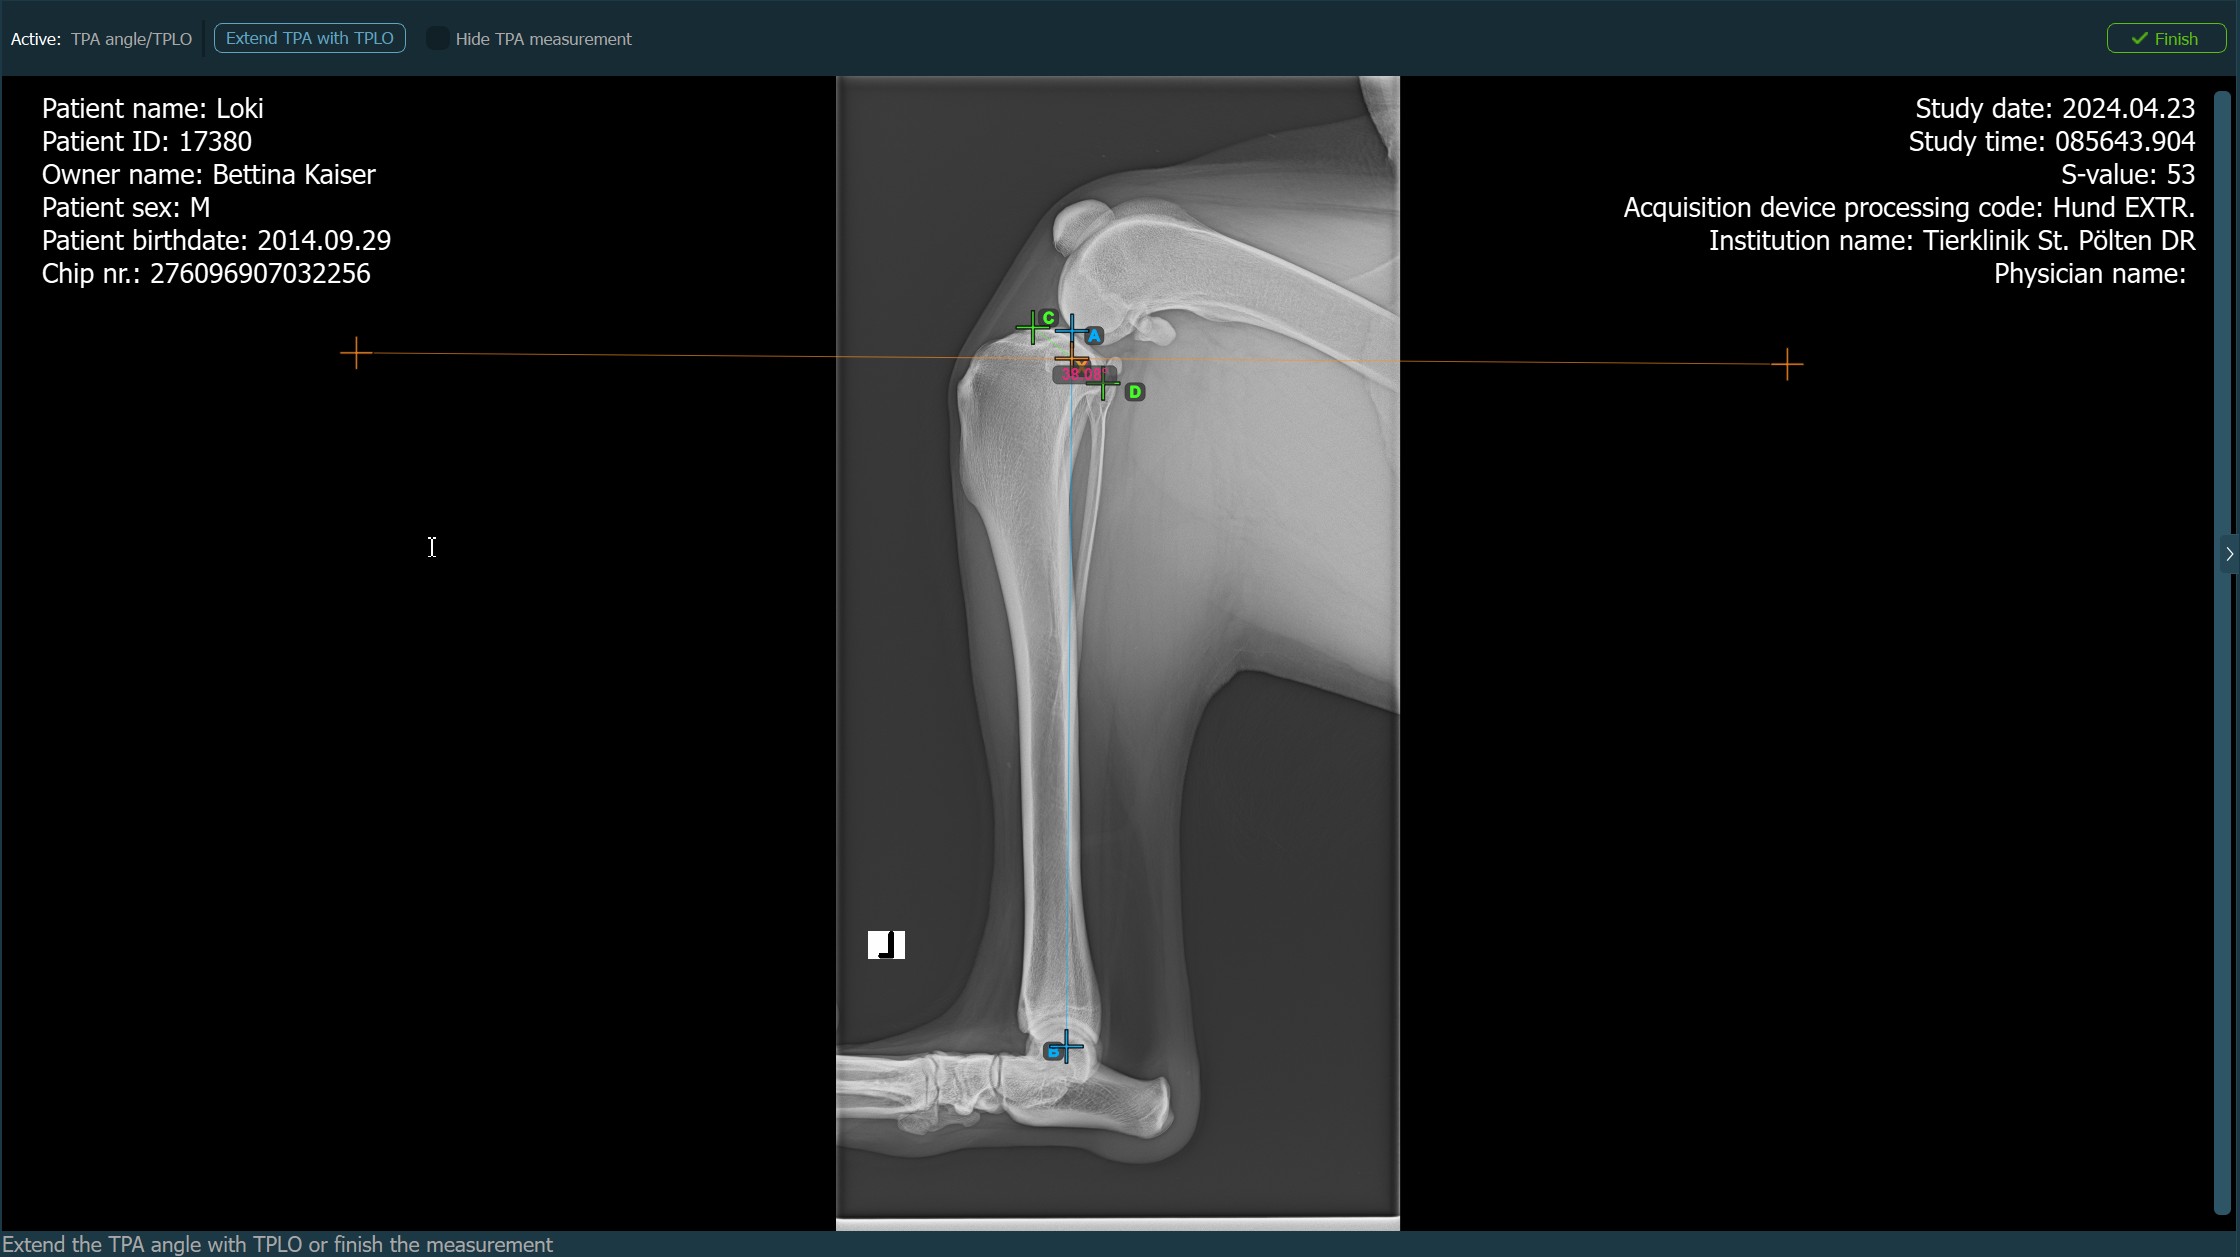

When the TPLO extension to the TPA Angle measurement is enabled, choose one of the available options from the advanced measurement mode toolbar to continue/complete the measurement. The TPA Angle measurement is automatically completed otherwise.

Press

Finishto confirm and complete the TPA Angle measurement without the TPLO extension.Activate the TPLO extension by using the

Extend TPA with TPLObutton.Hide/Show the TPA Angle measurement during the TPLO extension by toggling the

Hide TPA measurementcheckbox.![]()

Start the TPLO extension by marking the tibial crest. The sawblade size for the TPLO extension is automatically calculated as the distance between the Eminentia Intercondylaris and the point located two thirds along the line connecting the most caudal point of the tibial head and the tibial crest.

The image below depicts the usual placement of the tibial crest point on the tibial head.